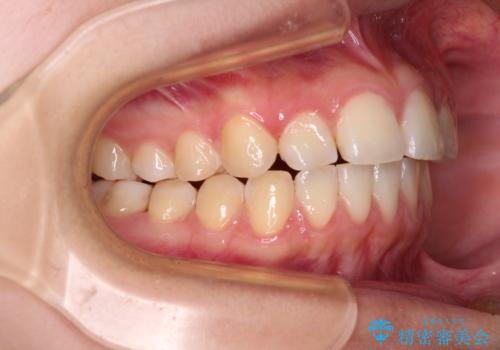

- 前歯の叢生を気にして来院された患者様です。

奥歯の咬み合わせを見ると、上顎が下顎に対して相対的に前方にあり、上下の前歯が接触していない状態でした。

咬み合わせを改善するためには、上顎臼歯を後方に移動させた咬み合わせにする必要があります。

インビザライン単体で改善することも可能ですが、咬合力が強く、単位で達成する可能性が低いと考えられたため、カリエール・ディスタライザーという補助装置を併用して、より確実性を上げることとしました。

奥歯の咬み合わせを改善しながら、並行してインビザラインで歯列を整えることとしました。